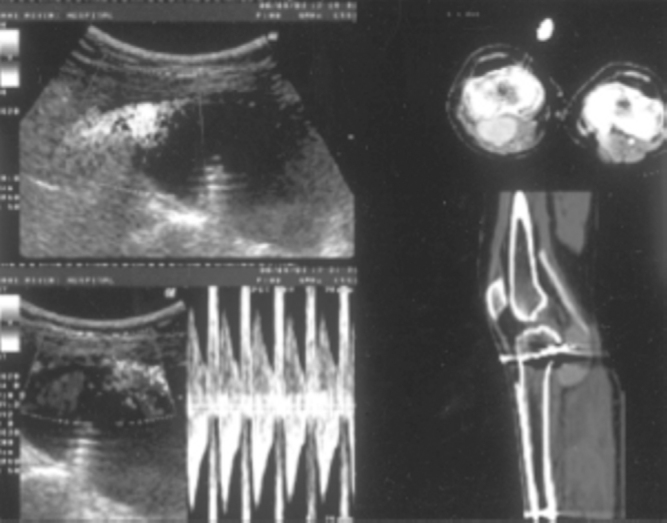

USGC was performed in seven cases, using a 7.5 MHz linear array color probe. All patients received analgesia and sedation prior to the procedure. The site of the arterial jet and the neck of aneurysm was localized and gradually compressed with the scanner probe obliterating the flow in the aneurysm sac without compromising parent artery patency. Compression was performed for 10 minutes, repeated maximally to three compressions per session. The patients were re-scanned within two weeks to confirm cessation of flow (Fig. 1).

Fig. 1.

Color doppler of left femoral artery, showing pseudoaneurysm following angiography. Initial USG scans reveal arterial leak and neck of aneurysm rescan during follow up after USG compression shows regression in pseudoaneurysm.

Pseudoaneurysm at inguinal region following catheterization, presents with a painful, pulsating enlarging groin mass, associated with a thrill and/or bruit. Pseudoaneurysm in kidney presents with recurrent and intermittent hematuria following procedures like PCNL, renal biopsy and occasionally after surgery. Coil embolisation is an effective modality in shutting down the offending pseudoaneurysm (Fig. 3A, Fig. 3B).

Fig. 3A.

Color doppler of right kidney in an adult male presenting with recurrent hematuria following PCNL shows pseudoaneurysm. Post embolisation color doppler images reveal obliteration with regression in size.